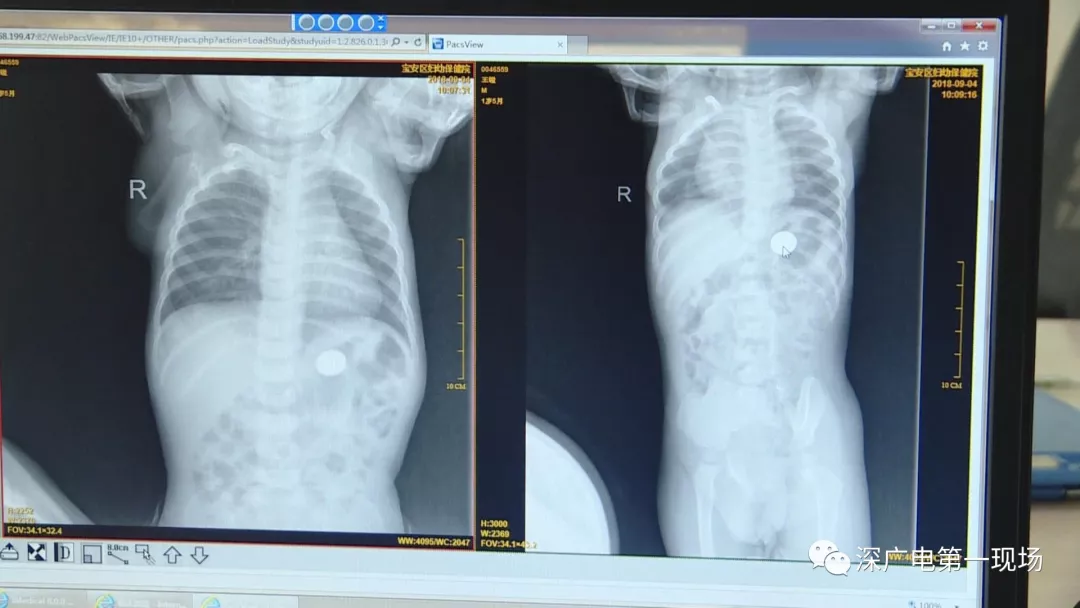

細心的醫(yī)生竟從

孩子的胸片中有了意外發(fā)現(xiàn)

胳膊摔骨折胸片里發(fā)現(xiàn)異物

9月4號,一名1歲零5個月的男嬰因在家中摔傷,被父母送到了寶安區(qū)婦幼保健院,醫(yī)生診斷為左側尺橈骨骨折。在進行全麻手術之前,院方例行對嬰兒進行了周身檢查。手術前,兒外科醫(yī)生趙冠聰在查看患者的胸片時,發(fā)現(xiàn)這名嬰兒的胃部有一枚硬幣大小的暗影。

胃部取出一角硬幣

已吞咽半月之久

經(jīng)過兩個小時的時間,兒科醫(yī)生郭景濤為患兒取出了藏在胃底的一角錢硬幣。目前,患兒已經(jīng)痊愈出院。